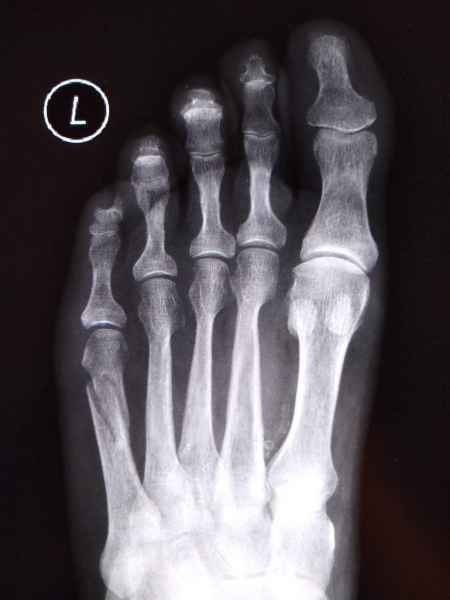

El pie es el órgano distintivo y característico de la especie humana, la única criatura que marcha erguida. El pie es una muy compleja estructura de arquitectura perfecta, adaptado a su función de apoyo, traslación, salto, con una riquísima sensibilidad que le permite detectar las más leves imperfecciones del suelo para estabilizar la marcha.

La marcha no solo es característica de la especie humana sino también de cada persona, y más aún varía según el estado de ánimo del momento. Una patología en los pies, se traduce en el rostro, en el ánimo, en el psiquismo. No sólo el dolor produce estos efectos, también un pie deformado o poco estético. En nuestra sociedad, la estética constituye un valor muy apreciado y estas alteraciones causan vergüenza fundamentalmente en las mujeres, que esconden en la playa sus pies en la arena y no pueden usar calzados elegantes.

Tanto la estructura del pie como su funcionalismo que es la marcha, pueden ser asiento y manifestación respectivamente de alteraciones locales ó sistémicas, por lo que su cuidadoso examen resulta de extrema utilidad diagnóstica.